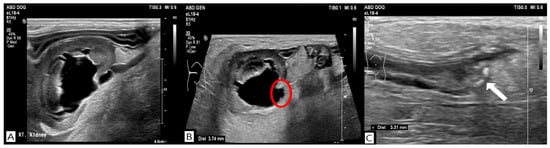

Bacterial culture of the renal pelvic fluid obtained during the procedure was negative results. However, because the sample was collected after the initiation of antimicrobial therapy, pyelonephritis could not be definitively excluded. Therefore, antimicrobial therapy was continued during hospitalization in consideration of leukocytosis, increased CRP concentration, and the high incidence of concurrent urinary tract infection [4]. Due to the financial constraints for surgery, medical expulsive therapy with tamsulosin (Hanmi Tams cap.®, Hanmi Pharmaceutical Co., Seoul, Republic of Korea; 0.1 mg/kg, per os [PO], once daily) was initiated. Because tamsulosin has been associated with adverse effects such as hypotension, dizziness, and gastrointestinal signs, the patient was closely monitored during treatment. SBP was measured using an oscillometric blood pressure monitoring device (Cardell® Insight Diagnostic Monitor, Midmark Corporation, Versailles, OH, USA). An appropriately sized cuff (SV2) was applied to the right forelimb and positioned as close to heart level as possible. Blood pressure measurements were obtained while the dog was seated and remained motionless. Prior to tamsulosin administration, the dog consistently maintained SBP values of ≥120 mmHg. Following initiation of tamsulosin therapy, SBP decreased to 97 mmHg at 12 h. Based on this reduction in SBP, although no overt clinical signs suggestive of hypotension were observed, the tamsulosin dose was reduced to 0.05 mg/kg once daily and subsequently maintained. Based on evidence that MET with tamsulosin combined with furosemide could be an effective for the treatment distal ureter stones in humans [12], furosemide (Laxis®, Handok Pharmaceuticals Co., Eumseong, Republic of Korea; 0.7 mg/kg, intravenously, three times daily) was added as adjunctive therapy to maintain the effectiveness of MET following tamsulosin dose reduction. No further episodes of hypotension were observed during furosemide administration. Follow-up ultrasonography confirmed spontaneous stone passage 3 days after initiation of tamsulosin therapy, with right renal pelvic dilation reduced to 3.99 mm and ureteral diameter reduced to 1.75 mm (Figure 4).

Figure 4. Ultrasonographic findings before (AC) and after medical expulsive therapy. Post-treatment ultrasonography on day 7 demonstrated a reduction in right renal pelvic dilation (D) and ureteral distention (red circle) (E), with no detectable ureteroliths (F).

Blood parameters also significantly improved, including SDMA (60 μg/dL), BUN (44.0 mg/dL), creatinine (1.9 mg/dL), and CRP (136.9 mg/L). Therefore, tamsulosin and furosemide therapy were discontinued. The dog remained hospitalized because of concurrent pancreatitis. Follow-up ultrasonography was performed on days 8, 9, and 11, and no recurrence of renal pelvic dilation, ureteral obstruction, or ureterolithiasis was identified. The patient was discharged on day 12 of hospitalization.